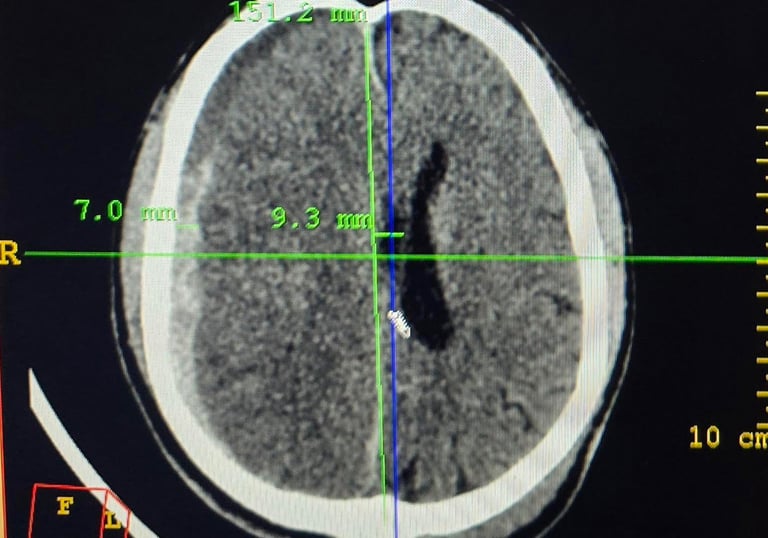

A Neurocirurgia é uma especialidade médica muito demandante. A importância de um bom exame físico seguido de exames laboratoriais e de imagem complementares permite o diagnóstico adequado e escolha da melhor terapia farmacológica e/ou cirúrgica para o paciente. Paralelo a isso, a importância de um bom equipário conforme complexidade do caso em questão levam a grande impacto na condução do caso: tomografia computadorizada, ressonância mangética, microscopia, aspiração ultrassônica, monitorização neurofisiológica intraoperatória, neuronavegação, dentre outros. Contar com um profissional que eticamente conduza o caso na luz do conhecimento científico fará diferença na sobrevida e é assim que seu quadro será conduzido!

Galeria de Imagens

Explore nossas cirurgias de coluna e neurocirurgia oncológica realizadas